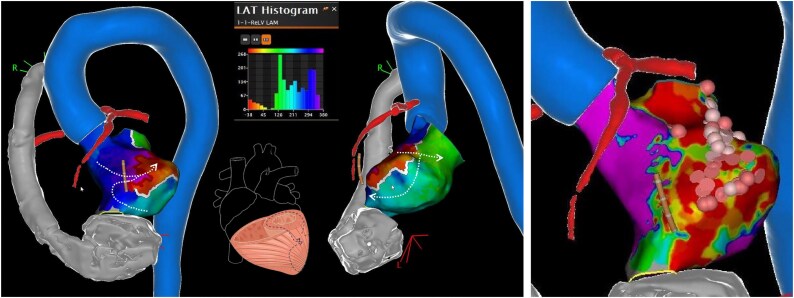

背景:室性心动过速(vt)是终末期左心室功能障碍患者的一种危及生命的并发症,也是考虑先进治疗的常见原因。在左心室辅助装置(LVAD)支持的患者中,他们的管理提出了独特的挑战,需要多学科的方法来定制策略。病例总结:我们报告一位有室性心动过速病史的70岁男性患者,因继发于缺血性心肌病和难治性室性心动过速的晚期心力衰竭而接受心脏伴侣3 (Abbott, USA)植入。在LVAD植入后,他开发了一种电风暴,对抗心律失常药物和射频和脉冲场导管消融的组合难以耐受。由于持续的VT,交感神经系统的神经调节被认为是最后的策略。经皮射频消融星状神经节不成功;而左侧交感神经切除术能有效控制心律失常。随访1年,患者无心律失常事件发生。讨论:LVAD携带者的室性心动过速的管理通常是逐步进行的,从纠正可逆的触发因素和使用抗心律失常药物开始。然而,单一治疗往往是不够的,实现心律失常的控制往往取决于多模式的方法。对于常规措施无效的病例,升级到导管消融、神经调节技术和立体定向心律失常放射消融可能是有效的。

Case summary: We present the case of a 70-year-old male with a history of VTs who underwent HeartMate 3 (Abbott, USA) implantation for advanced heart failure secondary to ischaemic cardiomyopathy and refractory VTs. Following LVAD implantation, he developed an electrical storm refractory to a combination of antiarrhythmic drugs and both radiofrequency and pulse-field catheter ablations. Due to persistent VT, neuromodulation of the sympathetic nervous system was considered as a last-resort strategy. Percutaneous radiofrequency ablation of the stellate ganglion was unsuccessful; however, left surgical sympathectomy effectively controlled the arrhythmias. The patient has remained free of arrhythmic events at 1-year follow-up.